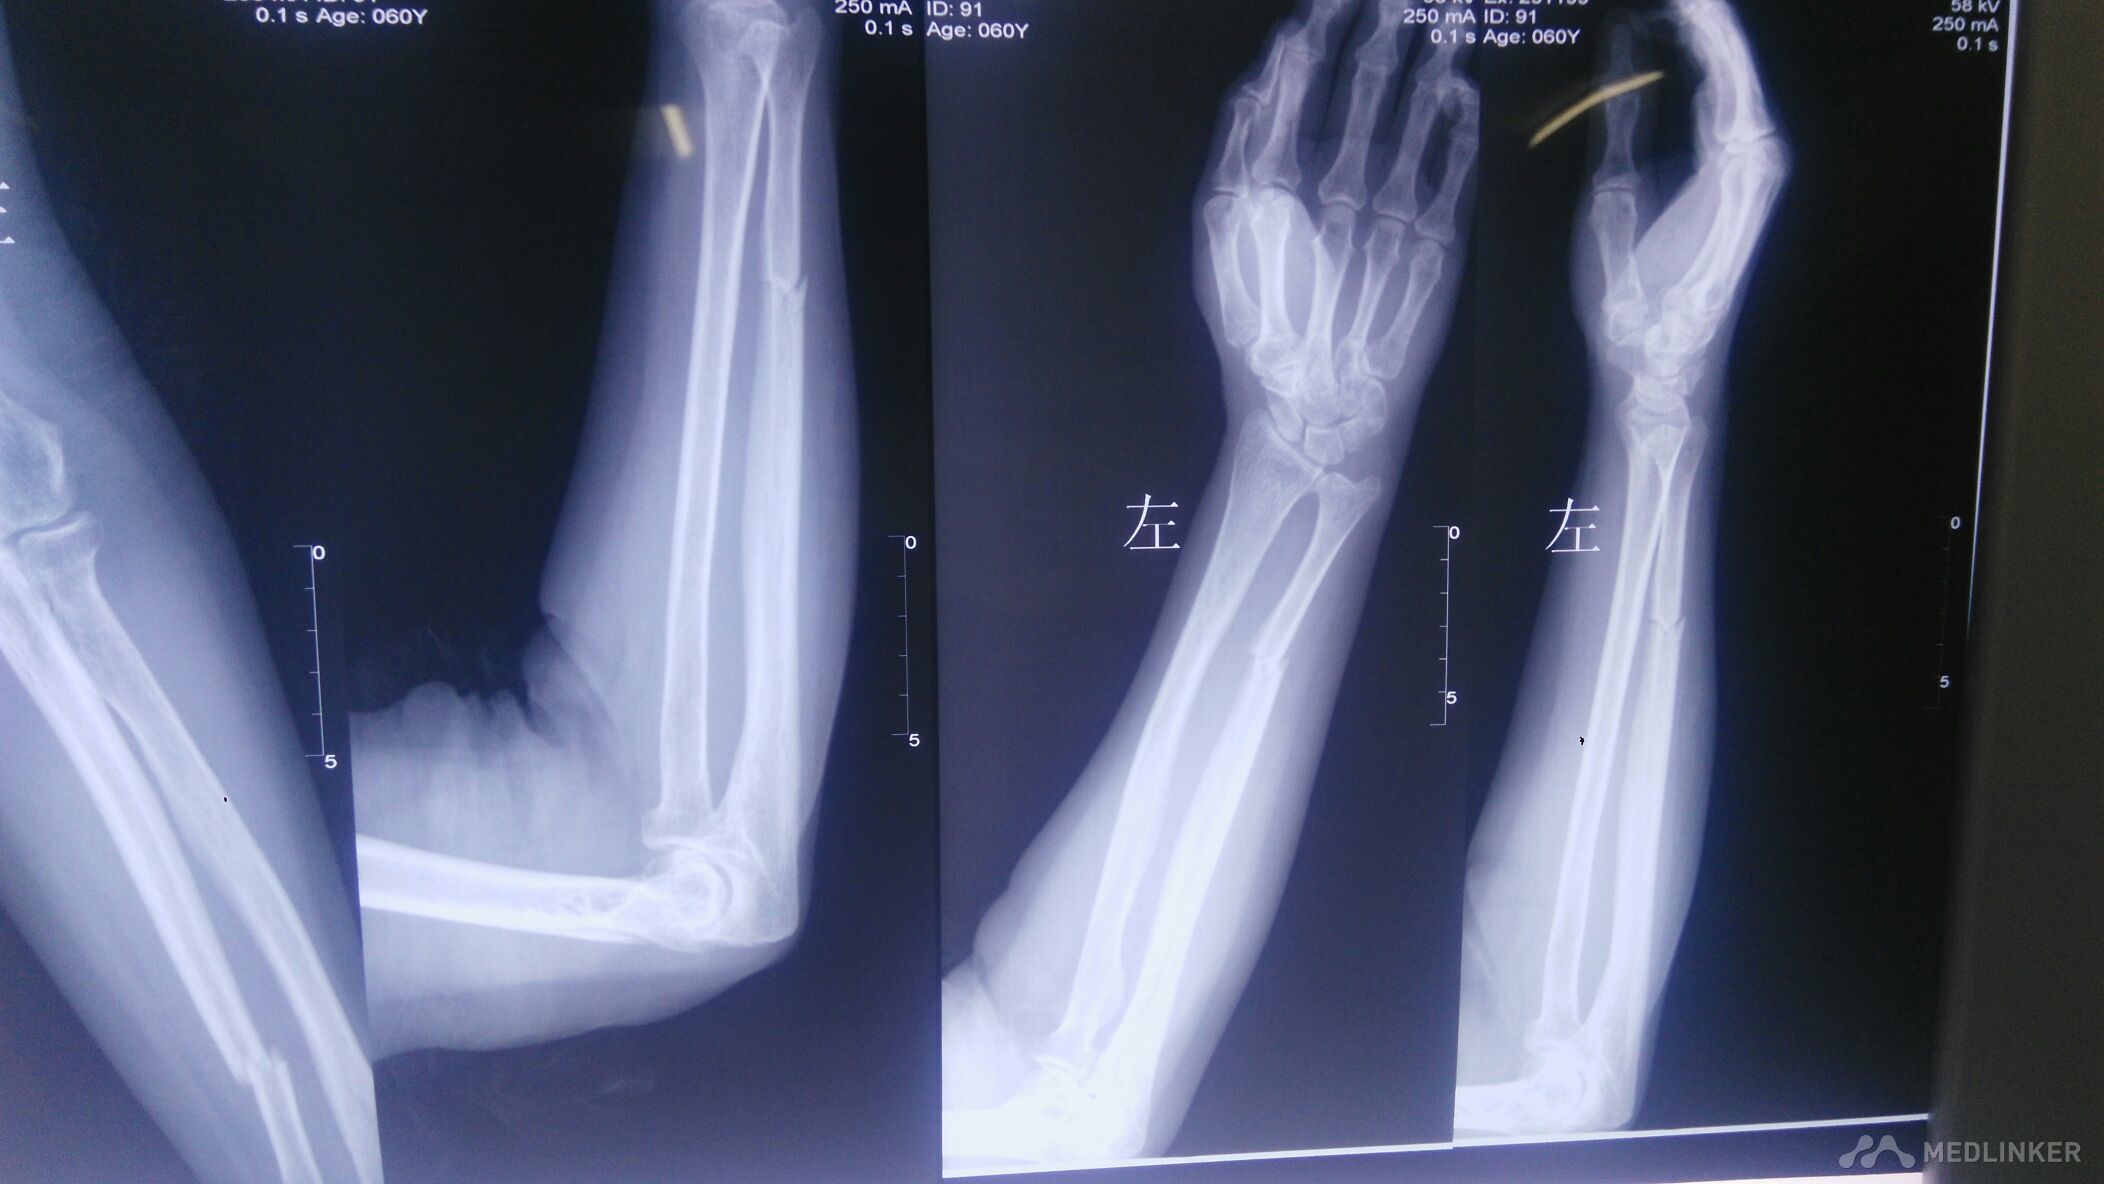

左侧尺骨骨折的治疗。

骨折 尺骨骨折

左前臂外伤后,尺骨肿痛,稍畸形。可触及骨擦感。左前臂活动受限。

骑电动车摔倒致左前臂肿痛3小时,左前臂以尺骨处压痛阳性,叩痛阳性。

左前臂尺骨骨折,给行保守治疗。

不复位吧,差一点,复位吧!担心复位过度,不如不复位。还是尽一把力吧!